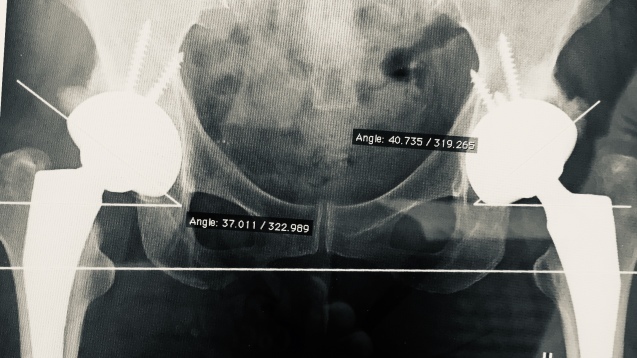

| 闘病日記